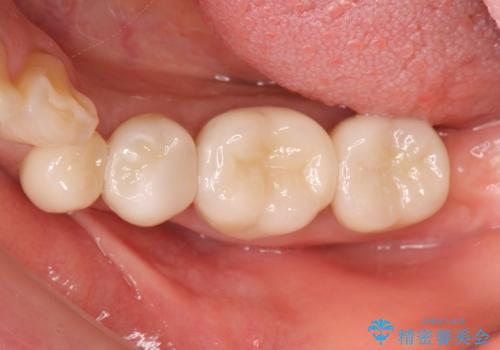

銀歯を除去したのち、虫歯を丁寧に除去し、歯を残せるのかどうかをしっかりと評価し、長期的な予後を見据えた虫歯治療を行っていきます。

- 154万円(インプラント×2・チタンカスタムアバットメント×2・ジルコニアクラウン×6・仮歯×6)費用は治療当時の料金となります

銀歯の下で虫歯が再発していた歯は、無理に残しても割れてしまう可能性が非常に高いと考えたため、相談の上抜去を行いインプラント治療を行っていくこととしました。